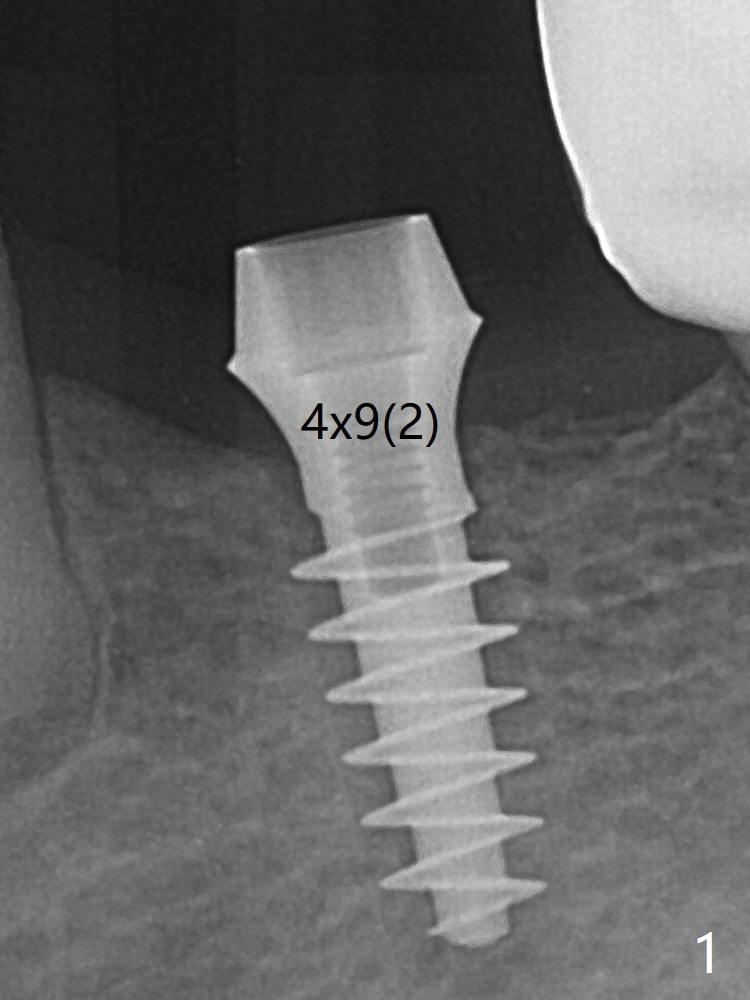

After finishing osteotomy at #19 according to IS drill sequence for 4x10 mm implant except cortical tap, a 4x9(2) mm Magicore is placed with ~ 50 Ncm (Fig.1). Thin threads are less traumatic with less bone loss. The implant with 4.5x3 mm solid abutment is stable for impression nearly 3 months postop (Fig.3). Appreciate the distinct thread pattern of Magicore 3 months 1 week postop, immediately post cementation (Fig.4).